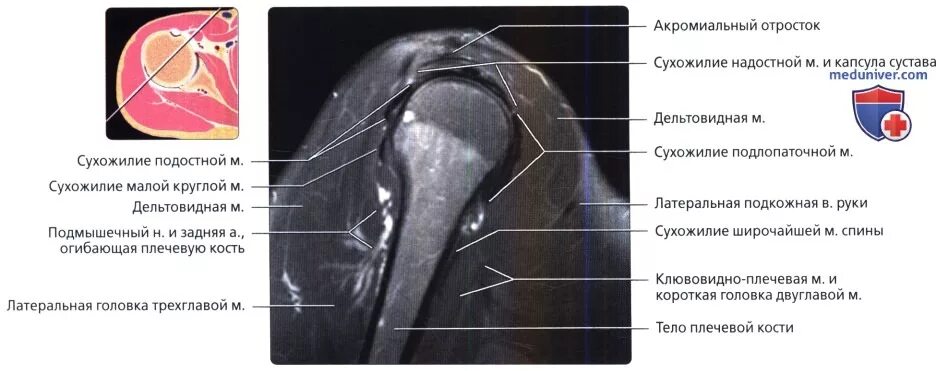

Лечение повреждения сухожилия надостной мышцы